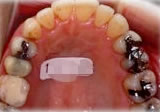

初診時年齢31歳7ヶ月。下顎側方偏位による咬合不全を主訴に来院。

顎変形と診断し、外科的処置を併用して治療。

上顎 上顎 上顎